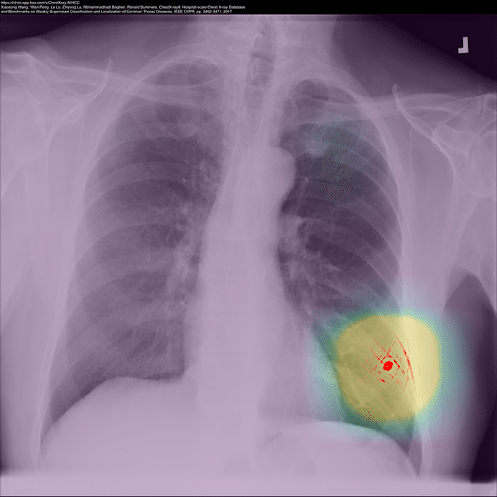

Preferred Networksは、現在医療向けAIなどの開発も行なってますが、例えばガン早期発見のための医用画像解析AIを作るための学習画像で患者の許可が明示的に必要になったとしても、「医療の発展のため匿名化した形で学習に使用させてください」と言えば同意する人も多いでしょうから「許諾学習」できるので問題ありません。